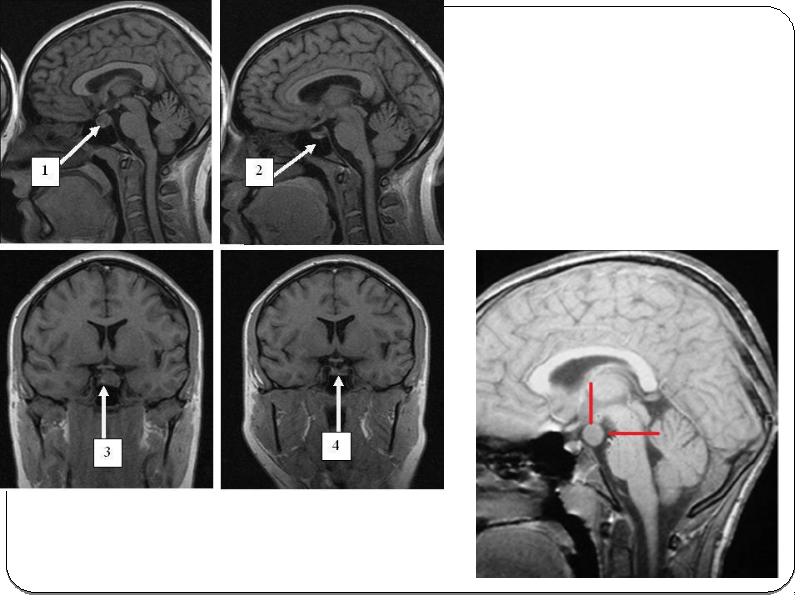

Синдром ханта лечение

Синдром ханта лечение 116 фото